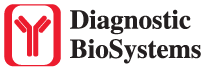

Iba1 (AIF1)

Actin-binding protein that enhances membrane ruffling and RAC activation. Enhances the actin-bundling activity of LCP1. Binds calcium. Plays a role in RAC signaling and in phagocytosis. AIF1 colocalizes with actin, and upon stimulation, translocates to lamellipodia. It is also a marker of human microglia and is expressed by macrophages in injured skeletal muscle. The gene encoding AIF1 resides in the tumor necrosis factor (TNF) cluster of genes, located in the region represented by the human major histocompatibility complex (MHC).

| Positive Control Tissue | Spleen |